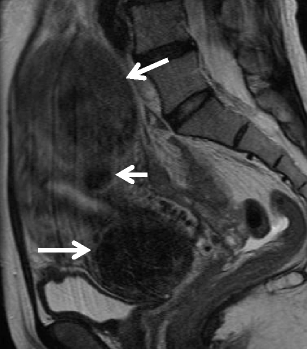

Small cell carcinoma in a 40-year-old woman. a Sagittal T2-weighted image demonstrates a polypoid mass of heterogeneous intensity in the endometrial cavity. The myometrium is diffusely thickened by diffusely infiltrating tumor. The cervix also is involved by the tumor (arrowhead). Extensive lymphadenopathy in the para-aortic region represents nodal metastases (arrows). b Sagittal contrast-enhanced T1-weighted images shows multifocal, unenhanced areas of necrosis